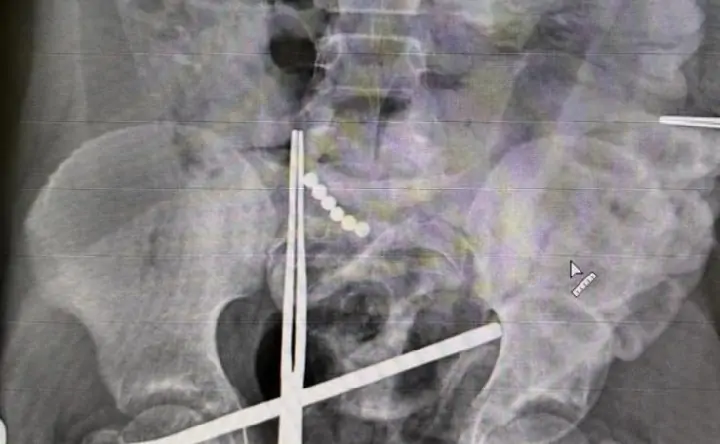

В Ростове 10-летний мальчик проглотил 19 магнитных шариков, и ничего не рассказал об этом взрослым, а через месяц поступил в больницу с острым воспалением внутренней стенки брюшины.

Как сообщили в Областной детской клинической больнице, ребёнку провели экстренную операцию: сначала шарики доставали через небольшой прокол в брюшной стенке, но без хирургического вмешательства закончить извлечение не удалось. После удаления инородных тел хирурги ушили отверстия в тонкой кишке ребёнка, которые успели проделать шарики.

Подобную операцию врачи проводили осенью прошлого года. Тогда хирурги достали из желудка мальчика 50 магнитных шариков. Болевых или дискомфортных ощущений у ребёнка не было, родителям о случившемся он сказал между делом. После этого родители обратились к медикам. Эндоскопическая попытка извлечь магнитные шарики оказалась безуспешной. И в итоге потребовалась очень полостная операция.